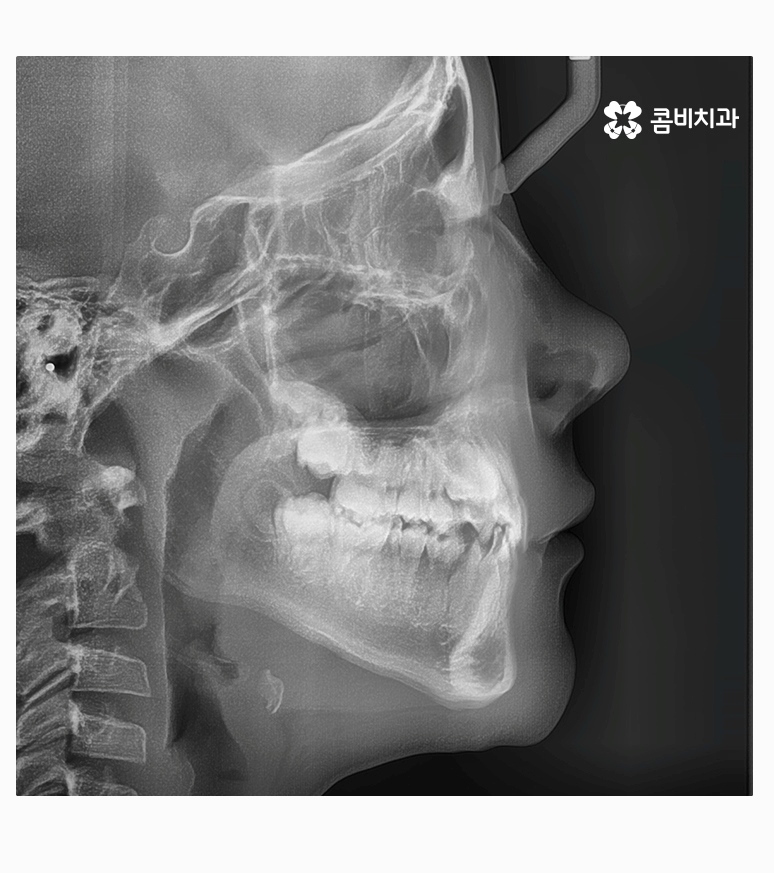

과개교합은 부정교합의 종류 중 하나라고 할 수 있으며

윗니가 아랫니를 정상보다 많이 덮고 있는 형태로 흔히 과개교합 혹은

피개교합으로도 불리고 있어요.

보통 윗니가 과도하게 돌출되어 있거나 치아의 크기가 큰 경우,

아랫니가 과하게 안쪽으로 들어가 있는 경우, 선천적으로 골격성 부정교합에

해당되거나, 이갈이 등 어금니에 과하게 힘이 가해지면서

마모되거나 치관의 길이가 짧아진 경우에

윗니가 아랫니를 덮고 있는 형태를 하게 될 수 있는데요.

성인이 되기 전, 성장기에 치아교정을 통해서 부정교합을

개선한다면 성장 조절을 통해서 비수술적인 방법으로 치료가

가능한 경우가 많고 성인이 된 후에 수술 혹은 발치를 해야하는

상황을 미리 예방할 수 있기 때문에 성장기부터 꾸준한

구강검진을 통해서 교합 및 심미적인 부분을 잘 개선해 주면 좋을 거예요.

부정교합을 치료하는 방법은 나이대와 어떤 상태인지 진단에

따라서 달라질 수 있는데 위 케이스처럼 일반적인 치아교정으로

진행이 되는 경우도 있고 구외 교정 장치를 활용하는 경우 등 진단에 따라 다양할 수 있어요.